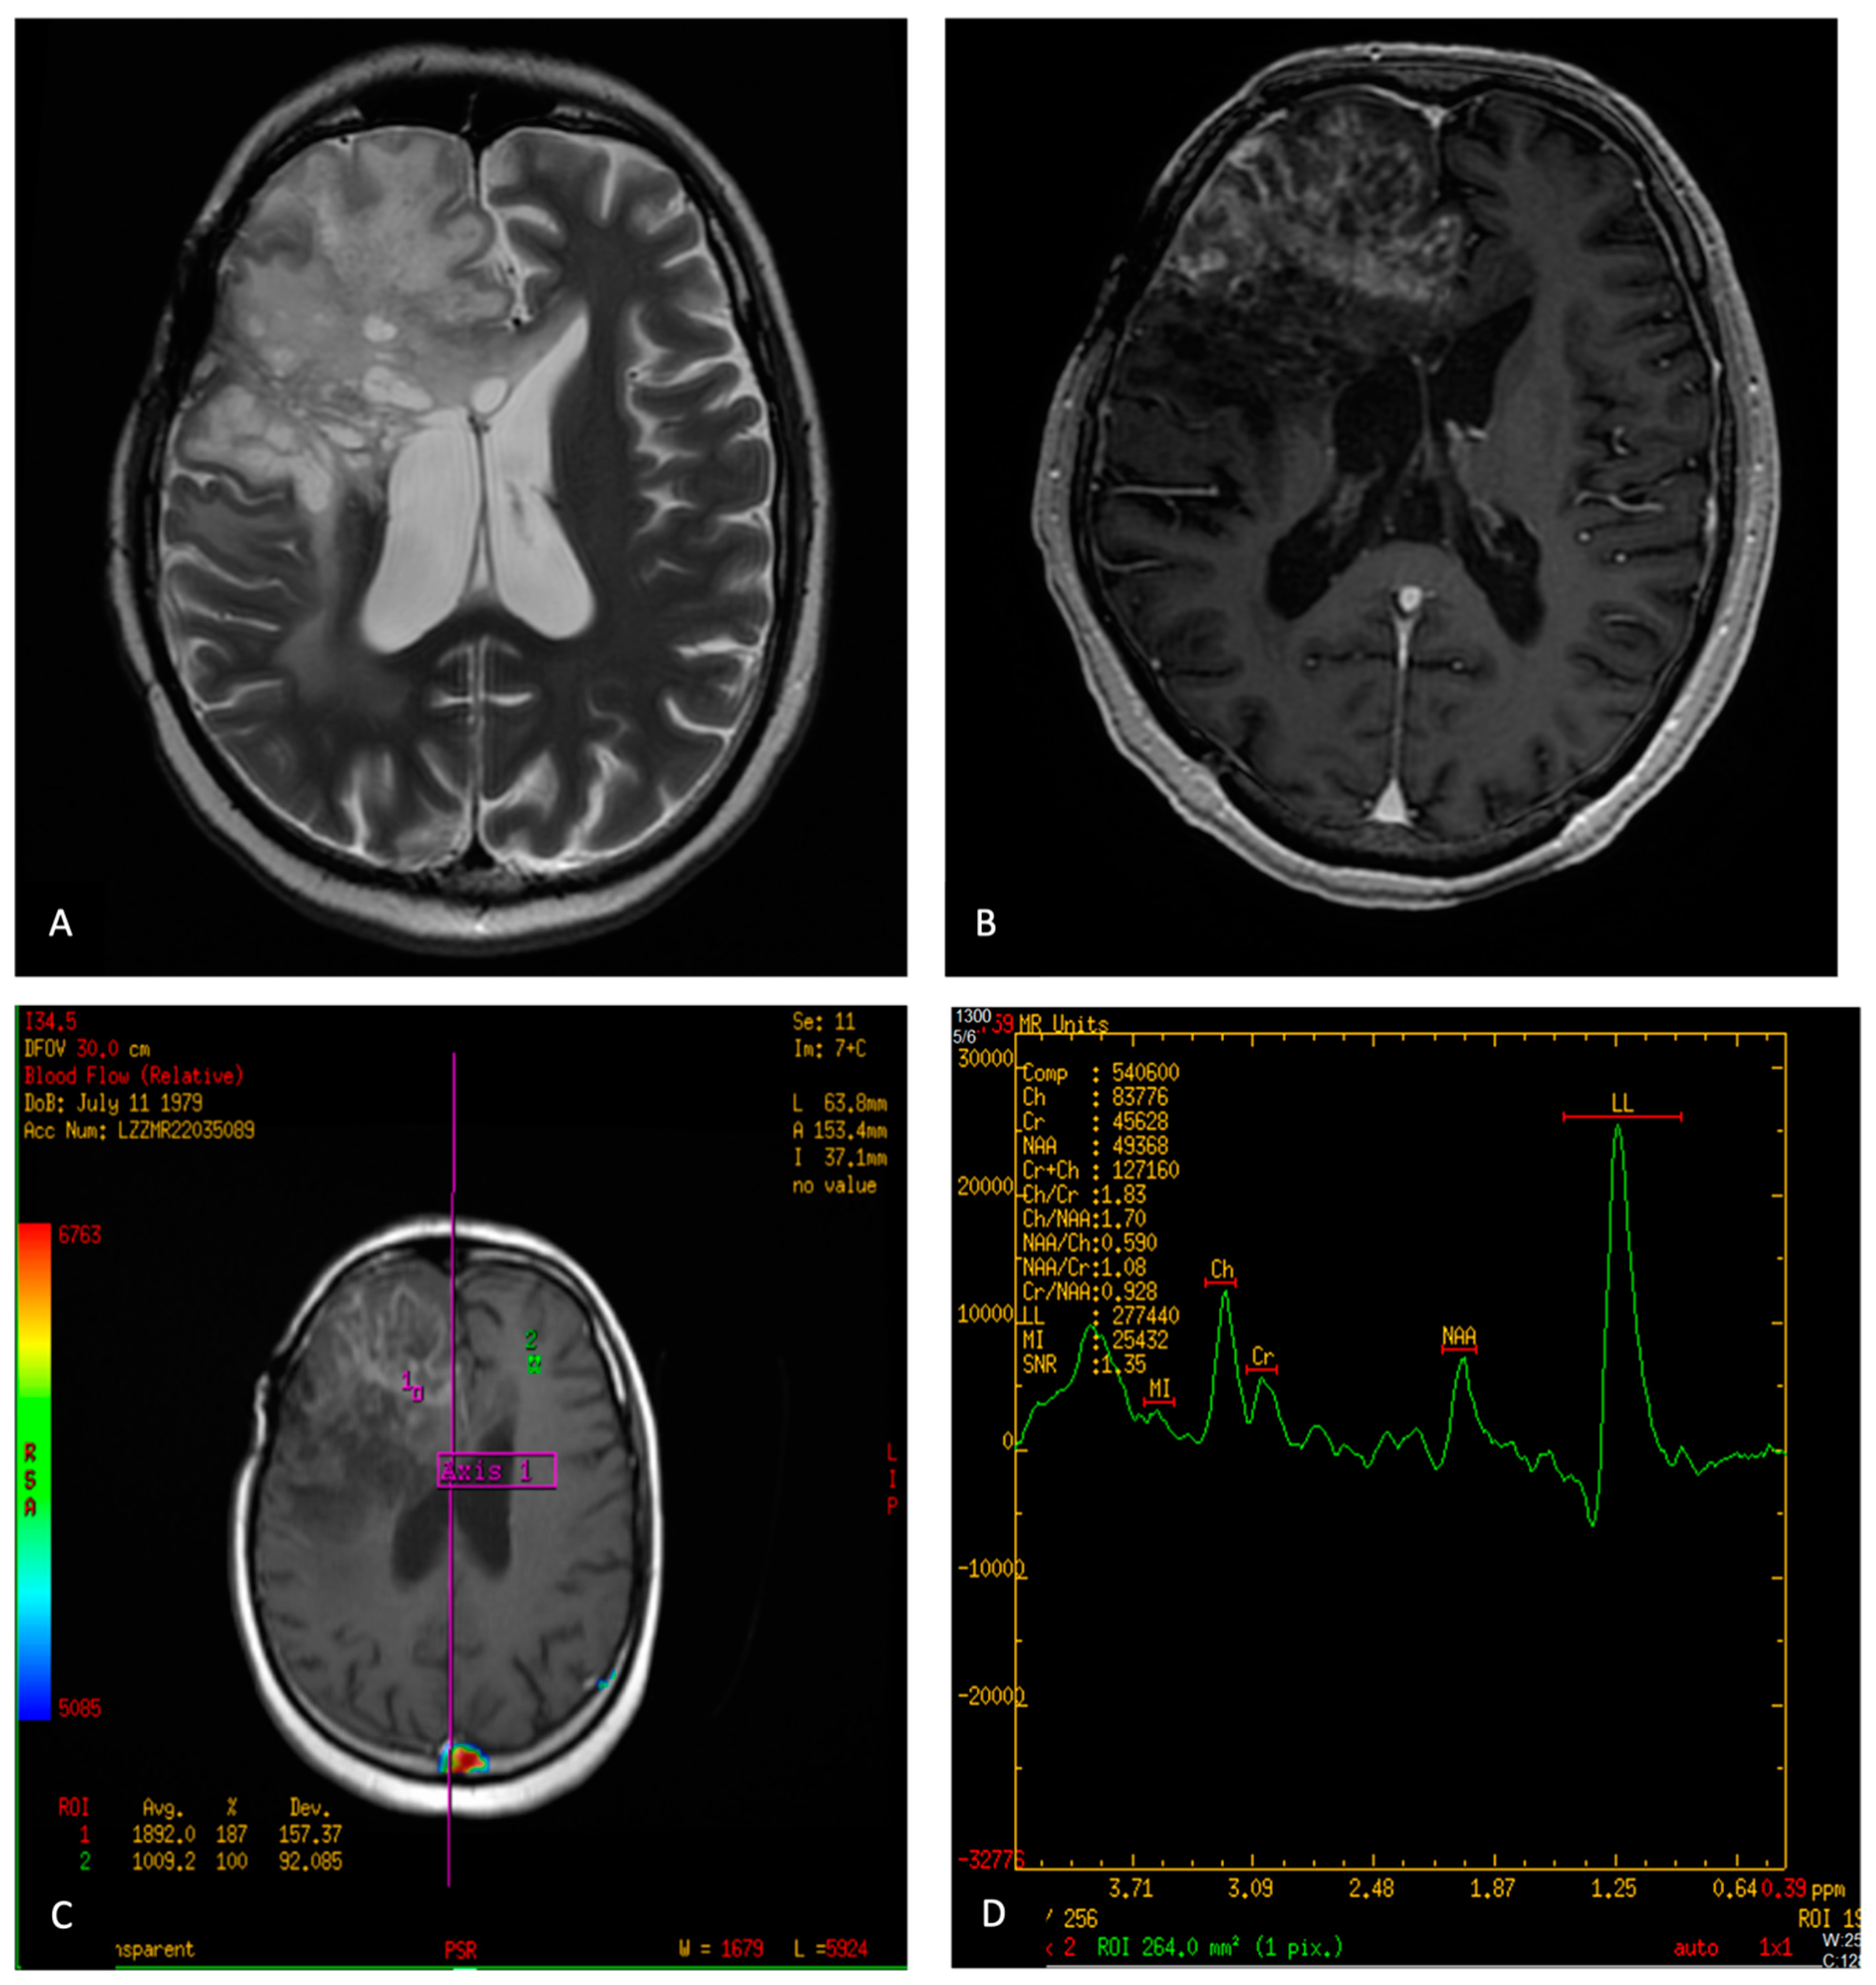

5.2. Diagnosis